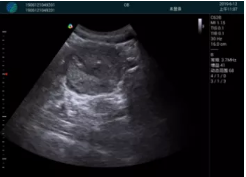

腺體內部清晰顯示一低回聲塊影,形態(tài)不規(guī)則,邊界模糊,邊緣呈毛刺狀,內部見砂礫樣鈣化

M20引導下穿刺活檢術

M20查看:囊內回聲均勻,邊界清晰,囊壁光滑

M20引導抽吸術后囊腫消失,原區(qū)域空腔形成,脂肪層與腺體層架構發(fā)生改變